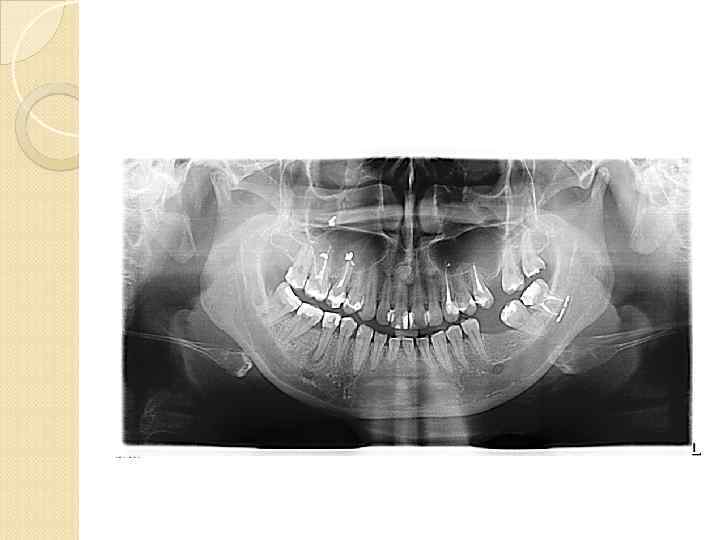

Сегодня рентгенологический метод исследования в стоматологии уже нельзя назвать вспомогательным. Ни одно хирургическое вмешательство не может считаться адекватным без рентгенологического мониторинга. Вильгельм-Конрад Рентген (1845– 1923)

Сегодня рентгенологический метод исследования в стоматологии уже нельзя назвать вспомогательным. Ни одно хирургическое вмешательство не может считаться адекватным без рентгенологического мониторинга. Вильгельм-Конрад Рентген (1845– 1923)

Однако для визуализации всех необходимых анатомических структур, выявления анатомо-топографических особенностей и патологических процессов челюстей вышеперечисленных методов рентгенографии бывает недостаточно рентгенограмма является двухмерным суммационным изображением и не позволяют исследовать объекты в

Однако для визуализации всех необходимых анатомических структур, выявления анатомо-топографических особенностей и патологических процессов челюстей вышеперечисленных методов рентгенографии бывает недостаточно рентгенограмма является двухмерным суммационным изображением и не позволяют исследовать объекты в

вследствие обязательных проекционных искажений, обусловленных технологией получения рентгенограмм, сложно произвести точные измерения.

вследствие обязательных проекционных искажений, обусловленных технологией получения рентгенограмм, сложно произвести точные измерения.

У пациентов с дефектами зубных рядов при подготовке к имплантации ортопантомограммы не всегда позволяют точно оценить степень атрофии альвеолярных отростков в различных плоскостях, четко рассчитать расстояние от альвеолярного гребня до важных анатомических образований

У пациентов с дефектами зубных рядов при подготовке к имплантации ортопантомограммы не всегда позволяют точно оценить степень атрофии альвеолярных отростков в различных плоскостях, четко рассчитать расстояние от альвеолярного гребня до важных анатомических образований